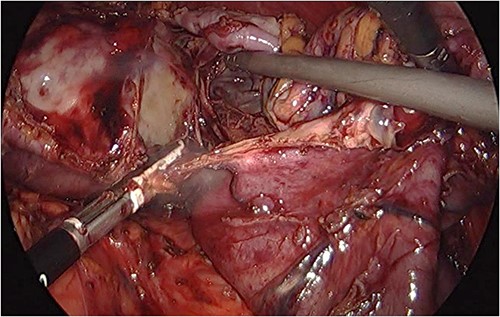

Preoperative prophylactic antibiotics and anticoagulant were given upon induction of anesthesia. The abdomen was accessed safely using a 5-mm vesiport under the guidance of the camera to the left and above the umbilicus. The remaining ports, a 15-mm port 5 cm at the right and above the umbilicus, a 5-mm ports at the left upper quadrant and 5-mm ports at the right upper quadrant were placed with no issues. The cyst was located at the lower pole of the spleen (Fig. 3). The operation consisted of opening the cyst and aspirating dark fluid, removal of the cyst wall (Fig. 4), cauterizing the part of the cyst adherent to the spleen, packing the surgical area with the omentum and removal of the specimen (Fig. 5). The postoperative period was uneventful. The final pathology showed a cyst wall lacking epithelial lining confirming the diagnosis of a pseudocyst, and the cystic fluid showed no malignant cells.